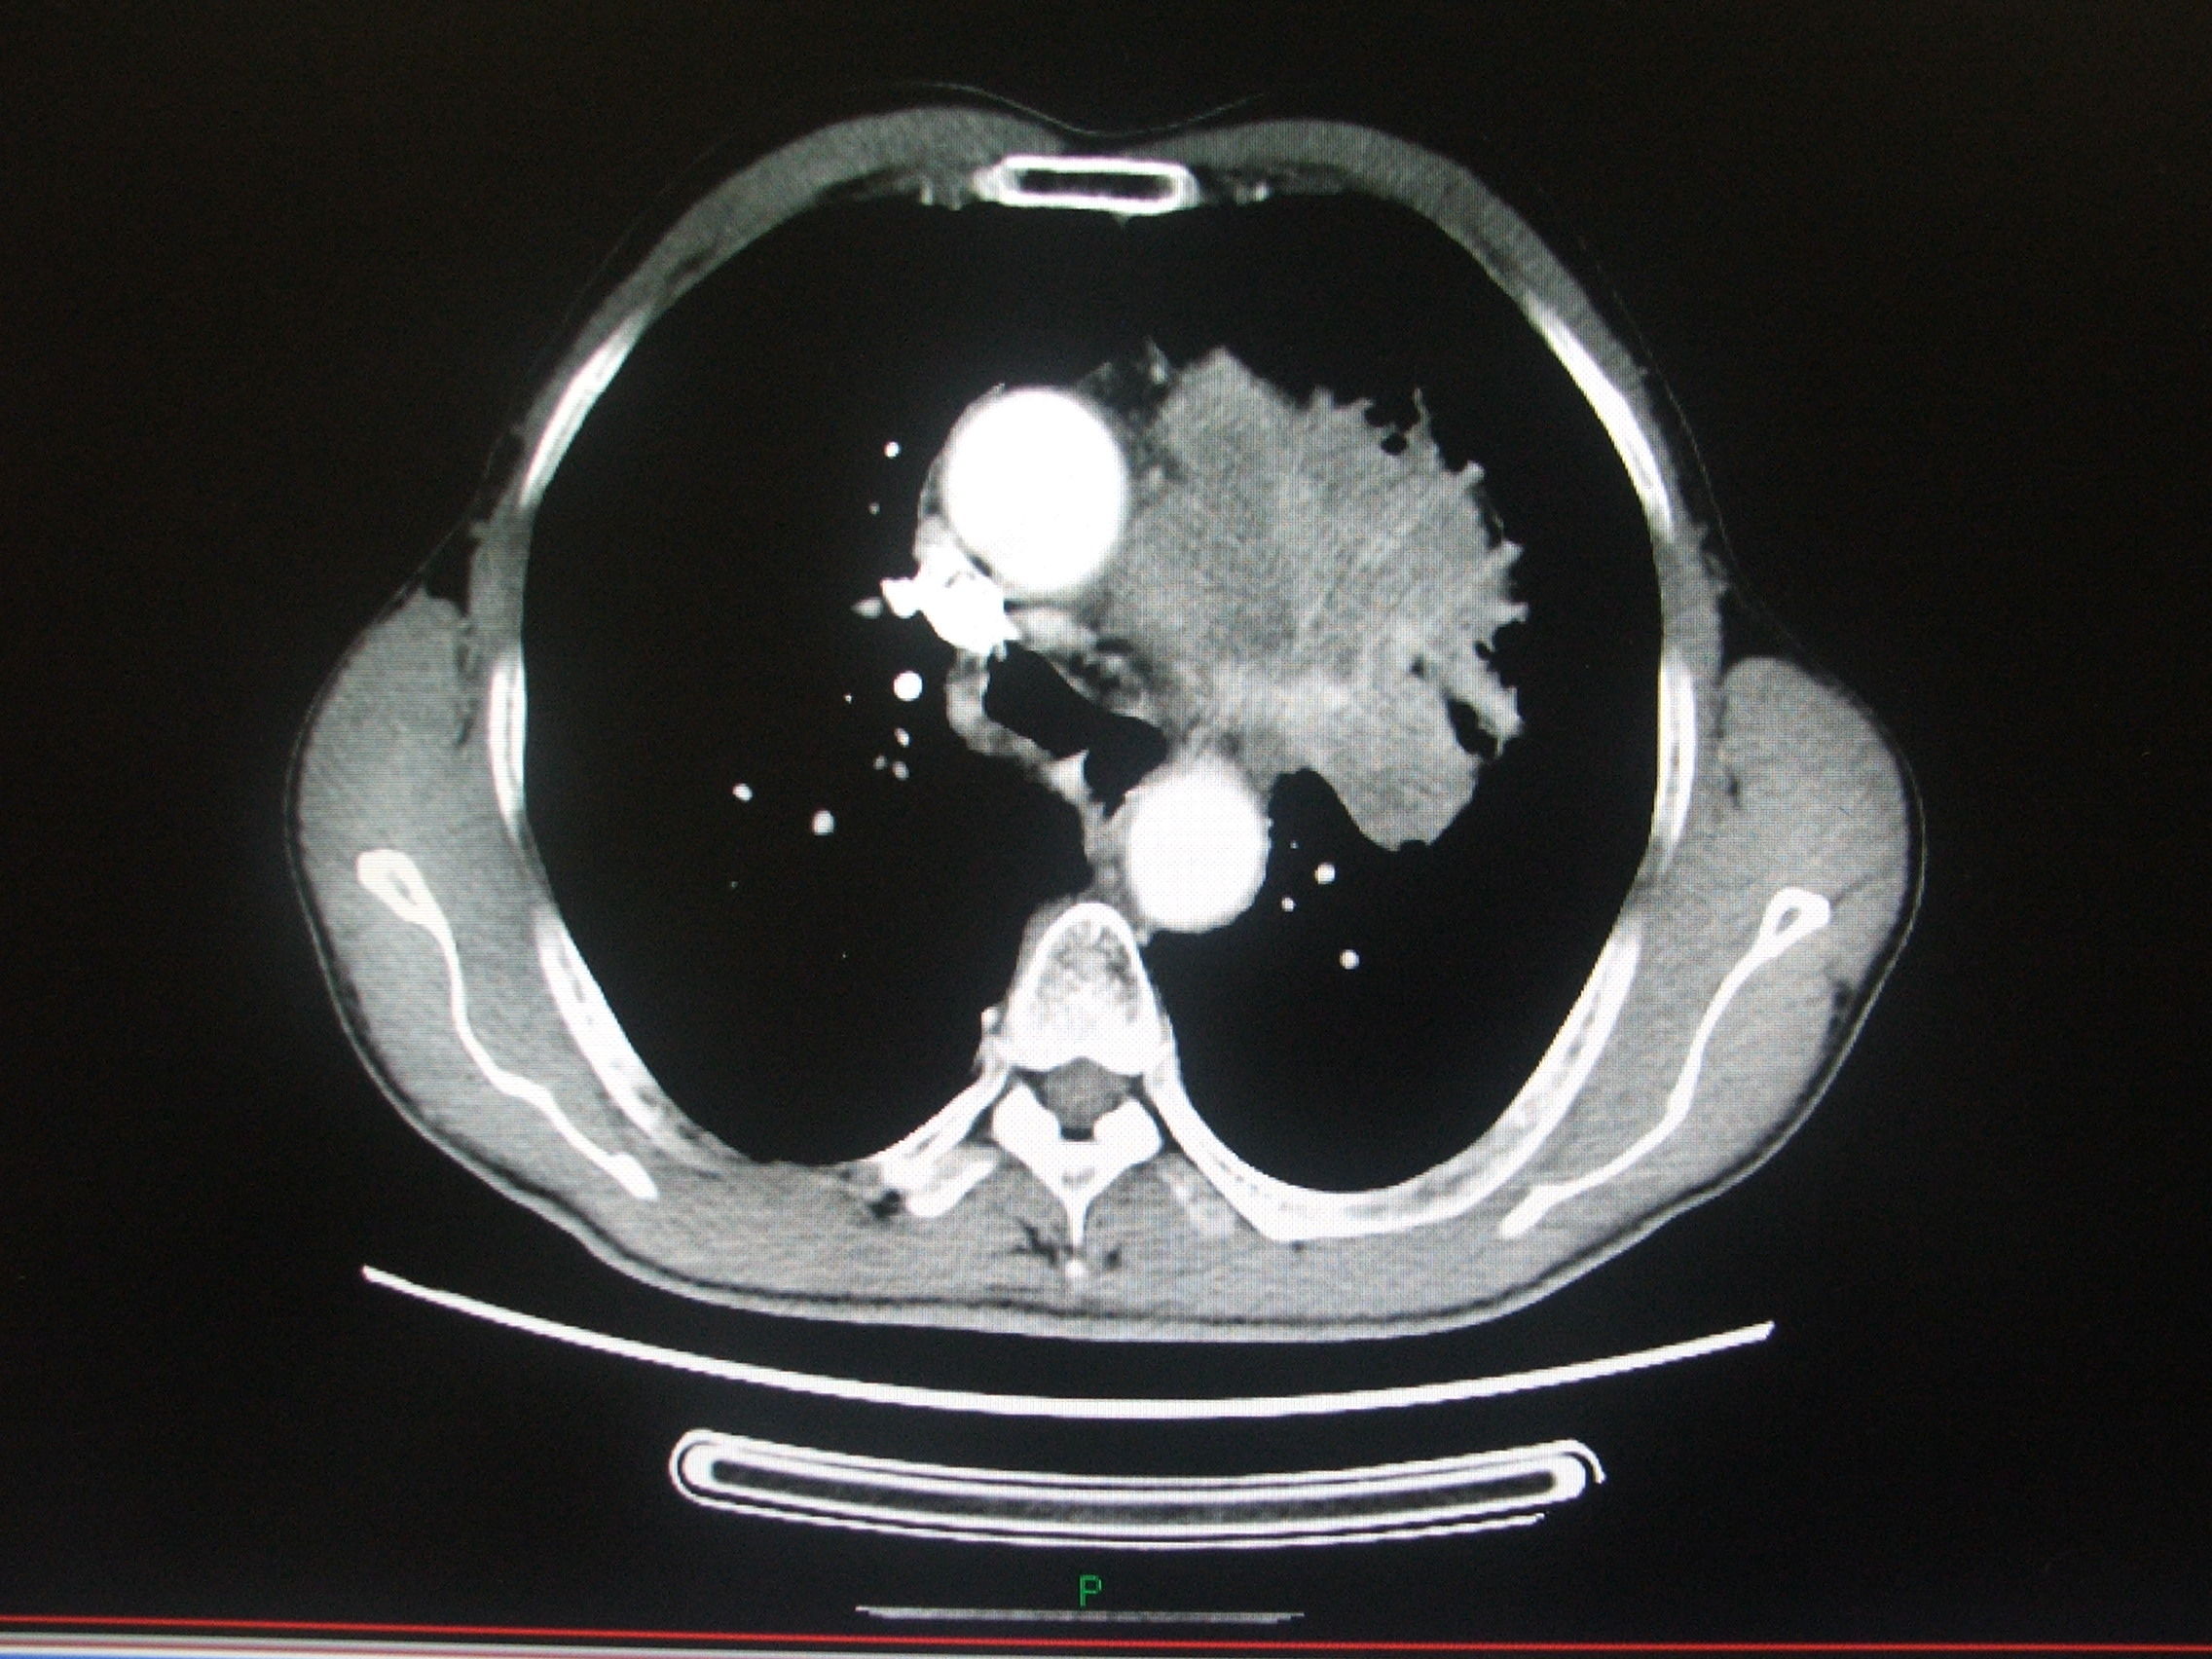

肺癌图片与正常肺图片[b0]肺部肿瘤是指发生在肺部的异常新生物分为良性肿瘤和恶性肿瘤两大类[b1]肺肿瘤和肺癌的图片肺癌长在肺叶上吗左肺囊肿是什么意思七七岁肺癌[b2]微创介入显身手不开刀消灭肺肿瘤[b3]全网资源[b4]肺肿瘤的恶性程度不能单凭大小判断[b5]肺肿瘤5cm良性几率多大当得知肺肿瘤长到5cm这样的尺寸时患者的内心[b6]老年男性右上肺结节大小16厘米手术明确浸润性腺癌老[b7]中央型肺部鳞状肿瘤能否实现治愈[b8]肺鳞癌术后复发[b9]肺上长了肿块不一定都是肺癌75岁女性2月来胸闷当地[b10]肺部病灶通过立体定向放疗之后这个肿瘤一个月之后复查已经消失了[b11]肺腺癌知多少一文带你揭秘这个肺事[b12]肺早期肿瘤究竟有多大一文读懂[b13]肺癌恶化最快的三种癌是什么肺癌是肺部的一种恶性肿瘤疾病这种疾病[b14]就是我们超过5个厘米以上的这个肺部的肿瘤我们可以先通过微创介入[b15]肺上长了肿瘤并不意味着无药可救哦首先要明确肿瘤的性质是列栽[b16]一个53岁肺腺癌晚期的病例[b17]拒绝化疗选择精准微创[b18]纵隔肿瘤严重吗是不是癌症[b19]面对体检报告上的肺结节10mm很多人心中都会升起一丝担忧这个[b20]右肺两个恶性肿瘤病人不能趴着只能躺着穿刺针刚刚好微[b21]左肺巨大肿瘤的临床决策思路分享[b22]肺部肿瘤知多少良恶性质大不同[b23]肺上有肿瘤是什么病严重吗[b24]年初手术成功实施粒子精准覆盖肿瘤区域[b25]肺鳞癌知多少一文带你全面了解[b26]肺早期肿瘤大小有讲究[b27]我院这位住院患癌的患者是得了周围型的肺部患癌而且肿瘤还侵犯[b28]6mm的肺结节在影像学上是一个相对较小的发现可能是良性的也可能[b29]患者胸背疼一个月做了ct发现肺上大肿块病理为浸润性肺腺癌[b30]5个层面讲清楚肺癌医学科普[b31]肺小结节和大肺癌有很大的区别[b32]6厘米有肺血管穿行图1并且血管有增粗[b33]肺结节是肺部影像学上的一种表现可能由炎症感染良性肿瘤等多种[b34]肺结节与肺癌的关系别再被误导了[b35]这类肺结节基本不复发[b36]得了肺癌要科学治疗这位老大伯用药两次肿瘤明显缩小家人[b37]简述常见良性肺肿瘤及其影像学特点[b38]一个不起眼的肺结节长成一个大肿瘤其实是很[b39]肺腺癌和肺鳞癌到底有哪些区别[b40]肺部鳞状细胞癌的一般存活年限是多少肺部鳞状细胞癌是一种非小细胞[b41]不开刀消灭肺肿瘤微创介入治疗快准狠[b42]患者因为胸痛就诊河津市人民医院行ct检查发现肺上长了个肿瘤[b43]瑞金胸外病例拾萃10肺类癌的诊治[b44]肿瘤2点5公分肺癌属于几期当发现肺部有一个2[b45]肺癌ct影像全解析带你读懂肿瘤信号[b46]重燃患者生命之光山东省第二人民医院肿瘤内科联合多学科精准施治肺巨[b47]12mm肺结节是肺癌几期你了解多少[b48]2cm部分实性结节恶性张力高病理浸润性肺癌磨玻璃[b49]肺结节的原因多种多样可能是由感染炎症良性肿瘤恶性肿瘤等导致[b50]202487天津医科大学总医院肺部肿瘤外科副主任医师[b51]肺结节和钙化灶是肺癌的前兆吗[b52]肺鳞癌是什么癌症[b53]2024516天津医科大学总医院肺部肿瘤外科副主任医师[b54]1肿块体积显著增大晚期肺癌的肿瘤体积[b55]肺结节癌变前可能出现的6种表现抖出健康知识宝藏[b56]肺结节早期肺癌一文解读肺部ct报告[b57]肺癌是恶性肿瘤疾病随着病情的发展可能会导致癌细胞出现远处转移[b58]1厘米的肿瘤[b59]

这个月的复查结果糟透了,肺上肿瘤疯长,已经发生了一次咳血。现在没有[s0]射波刀后肿瘤会消失吗[s1]是不是做了肺部穿刺就一定是肺肿瘤或者肺癌?[s2]图片[s3]肺上长肿瘤严重吗 小红书[s4]肺上良性肿瘤怎么办才能消除[s5]确诊为肺癌晚期。医生告知王阿姨,肿瘤发展较快,手术治疗的机会不大。[s6]后,医生的诊断结果让所有人震惊——是肺部恶性肿瘤,且已经是晚期了。[s7]右肺尖肿瘤,16个月迅速长大[s8]吸烟30年,虽已戒烟5年,但这个患者的肺黑得吓人,肺上的恶性肿瘤更加触目惊心![s9]岳母肺部肿瘤病情演变[s10]肺部肿瘤[s11]新方法可能减少肺部肿瘤的生长[s12]微信图片_20190404112215.jpg[s13]胸部肿瘤综合治疗之一肺癌篇~~~科大二附院胸外科胡举副主任医师治疗体会[s14]考虑肺部肿瘤[s15]肺部的恶性肿瘤[s16]肺部肿瘤[s17]右肺上叶肿瘤,穿刺难度大,患者高龄基础疾病多,手术中并发症风险大。[s18]麻烦给看一下我的肺部有肿瘤吗?谢谢了?[s19]肺上肿瘤切除手术好做吗(肺部肿瘤位置尴尬)(1)[s20]肺部巨大肿瘤[s21]少见!6厘米巨大肺部肿瘤—兖矿新里程总医微创切除![s22]查发现患者肺部也有一个肿瘤,考虑患者原发肿瘤在肺部,脑部是转移瘤。[s23]右肺上叶贴水平裂的肿瘤,手术切除范围的考量(病例回顾)[s24]肺部长肿瘤的症状[s25]这是一名35岁女性,左肺上叶将近4厘米的肿物,没有任何症状,查体时才发现,4厘米的肿瘤都没有临床症状,还是很可怕的。腔镜下切除,淋巴结应该不至于有转移,还是略偏早期,但术后是需要靶向药物治疗或者化疗的,尽量降低复发概率。所以,肿瘤不能等有了症状再就诊,分期晚了医生也没有办法。[s26]以前照片[s27]患者高龄基础疾病多,手术中并发症风险大。术前ct见右上肺肿瘤术中操作[s28]肺肿瘤影像大汇总,看完深刻理解[s29]发展,甚至肺上的肿瘤已经缩小了百分之四十,于是在2019年1月3日出院了。在进行了四个疗程的治疗后,[s30]肺上长肿瘤严重吗 mip.haodf.com[s31]肺上长肿瘤严重吗 来自网易[s32]右肺尖肿瘤,16个月迅速长大[s33]肺肿瘤有哪些危害[s34]肺肿瘤[s35]肿瘤标记物虽然是正常的,但是咳嗽原因不明,ct却发现肺上长了肿物.[s36]肺部恶性肿瘤需要手术吗能治好吗[s37]肺上长了肿瘤必须要做穿刺检查吗?[s38]肺部肿瘤能治好吗[s39]